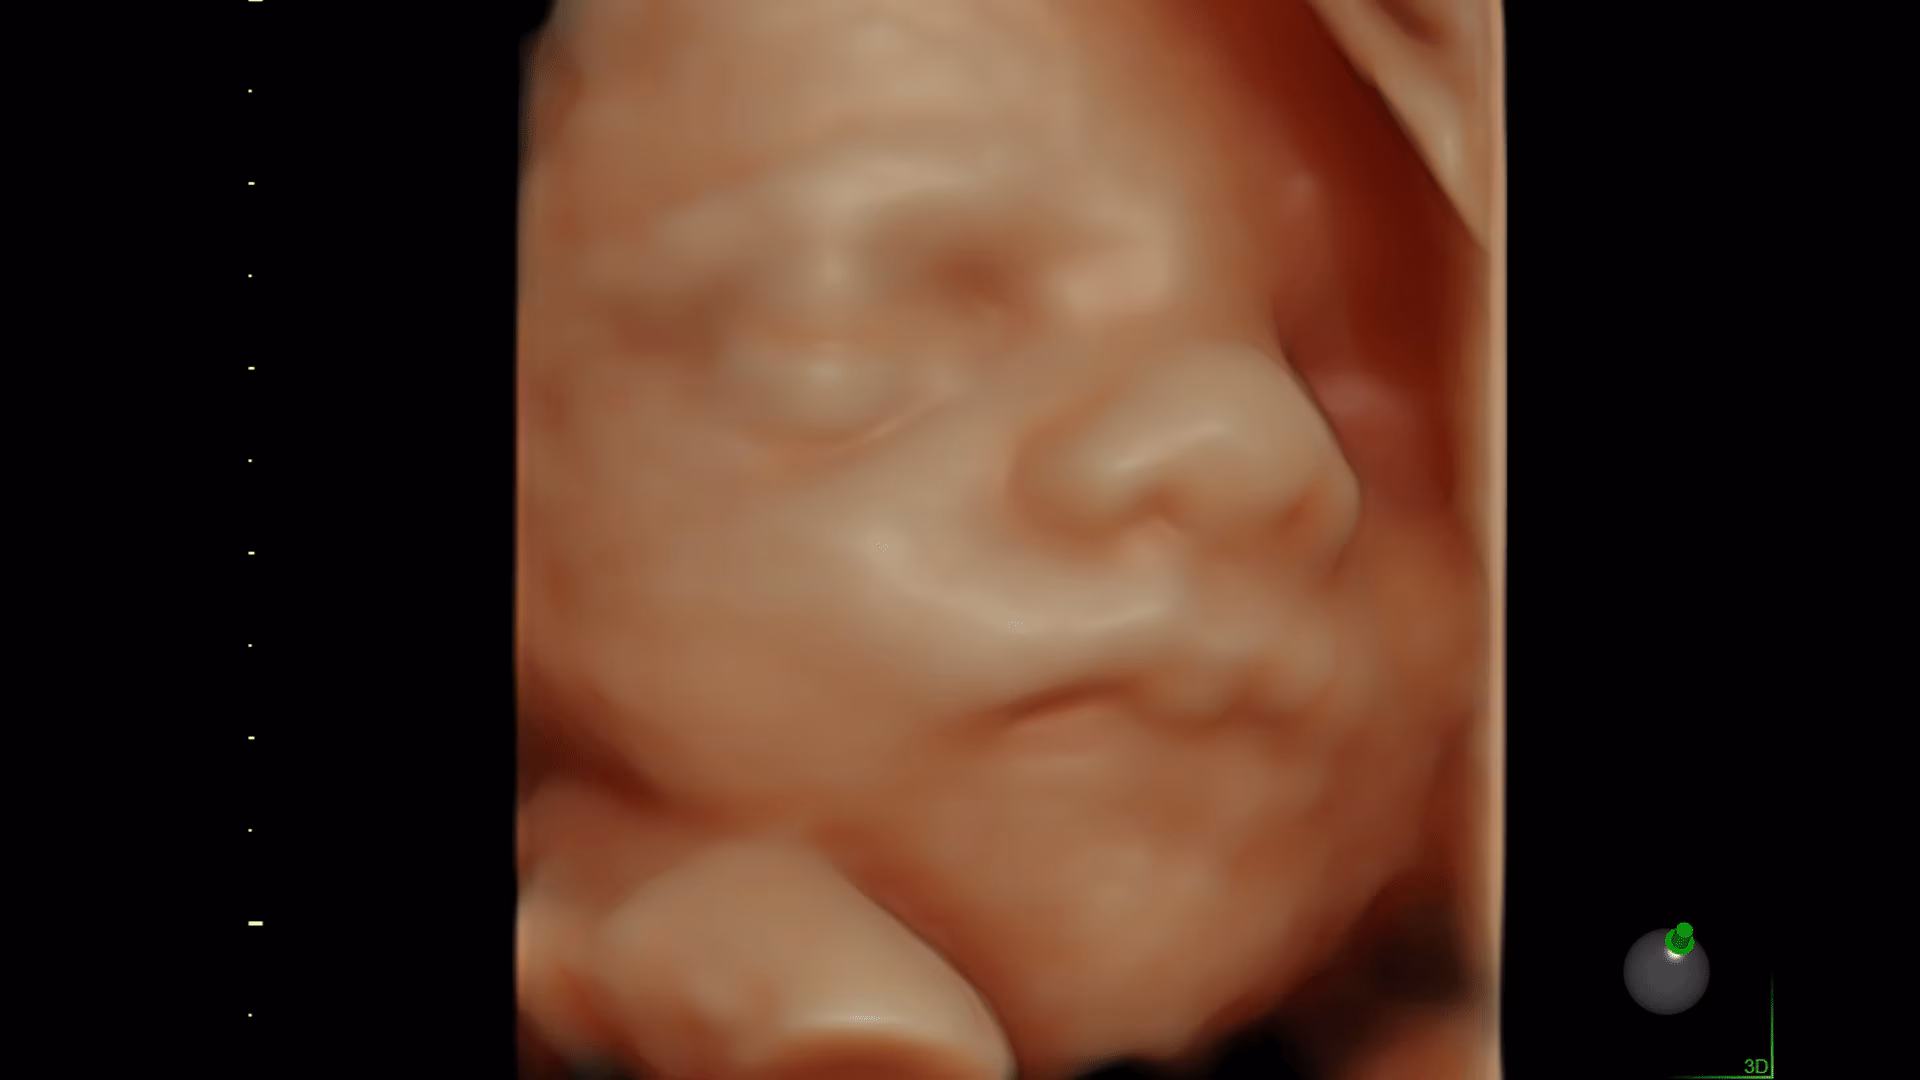

Sistema ecografico per ostetricia, ginecologia e fertilità

VOLUSON S8 con Touch panel

- HDlive: tecnologia di rendering 3D/4D di Voluson che trasforma i dati ecografici in immagini più realistiche con profondità, illuminazione e texture migliorate